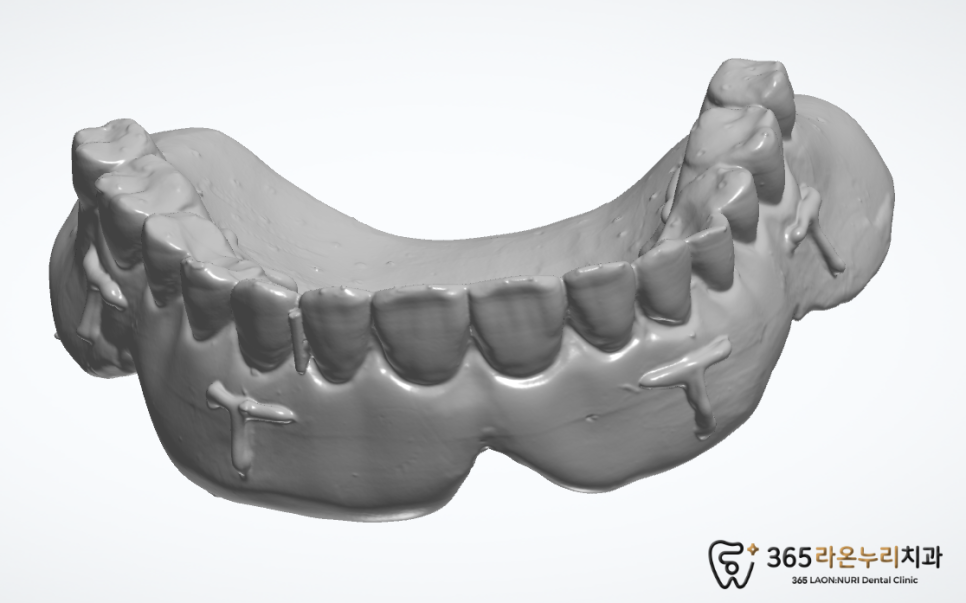

그리고 세마동 치과 에서는

식립 전 임시치아 제작을 위해

원래 쓰시던 덴쳐를 스캔을 해주었습니다.

2025.2.12

스캔을 진행한 덴쳐 스캔 파일을 확인해 보면

디자인 프로그램 안에서 병합할 수 있도록

“T”표시를 해주면 추후 임시치아 제작에

많은 도움이 됩니다.